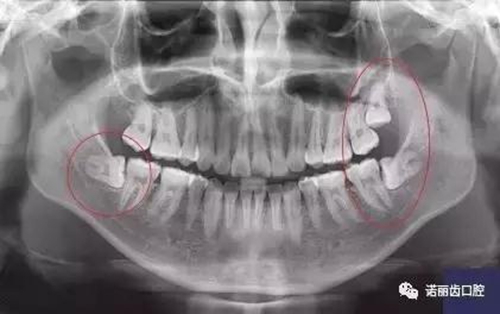

那么,如何判斷自己的智齒生長情況呢?除了有明顯的疼痛感你需要做相應的處理,同時通過X線可以觀察智齒的數(shù)量和位置以及具體情況。

經(jīng)過拍片探查,確定了以下情況的,那么,果斷的,禍患不可留啊: